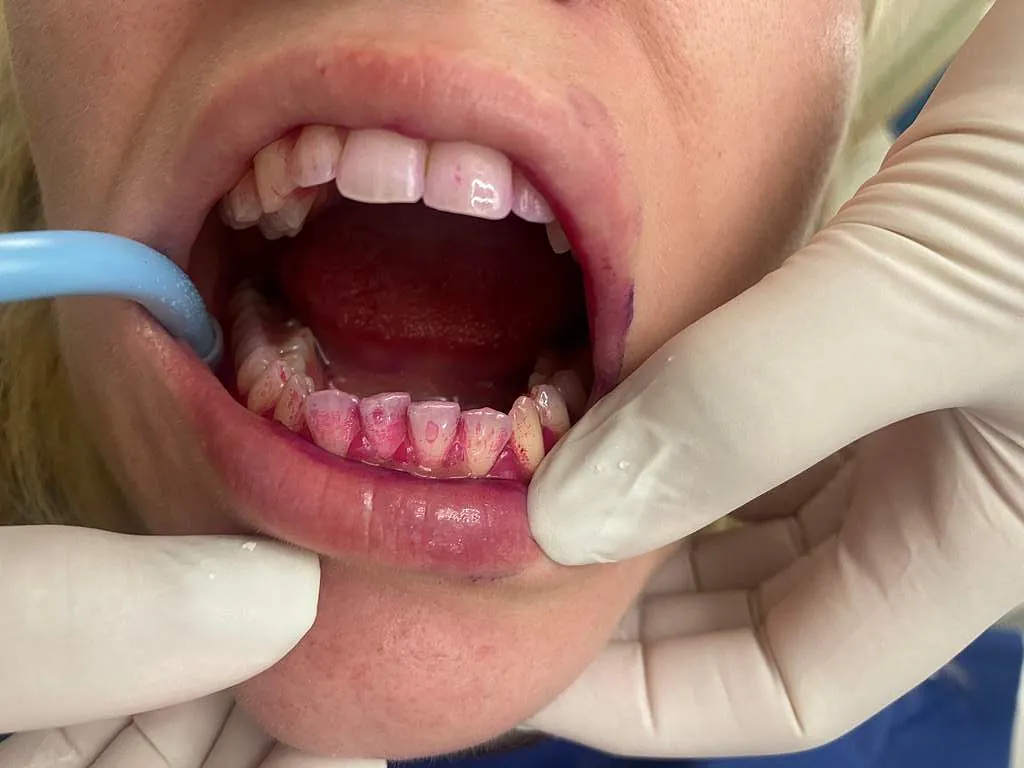

Περιστατικά που αντιμετωπίζονται στο ιατρείο μας

Στο ιατρείο ακολουθείται το νεότερο και πλέον σύγχρονο πρωτόκολλο θεραπείας (GBTguidedbiofilmtherapy), σύμφωνα με το οποίο ο οδοντιατρικός καθαρισμός, η θεραπεία ουλίτιδας και η περιοδοντική θεραπεία στη φάση ελέγχου της φλεγμονής και διατήρησης του αποτελέσματός της, πραγματοποιούνται με το πιο αποτελεσματικό, ήπιο και ελάχιστα επεμβατικό τρόπο.

Πέρα από τα δόντια, παθήσεις μπορεί να εμφανιστούν και στους ιστούς που στηρίζουν και περιβάλλουν τα δόντια (περιοδοντικοί ιστοί). Στην οδοντιατρική, οι νόσοι και οι βλάβες του περιοδοντίου (ουλίτιδα-περιοδοντίτιδα) αποτελούν τις πιο διαδεδομένες κύριες χρόνιες μη μεταδοτικές ασθένειες που αλληλοεπιδρούν και με σειρά από συστηματικές νόσους που μπορεί να έχει ο ασθενής (σακχαρώδη διαβήτη, ρευματοειδή αρθρίτιδα, καρδιακά νοσήματα, αιματολογικές διαταραχές, νόσοι του μεταβολισμού κ.ά.).